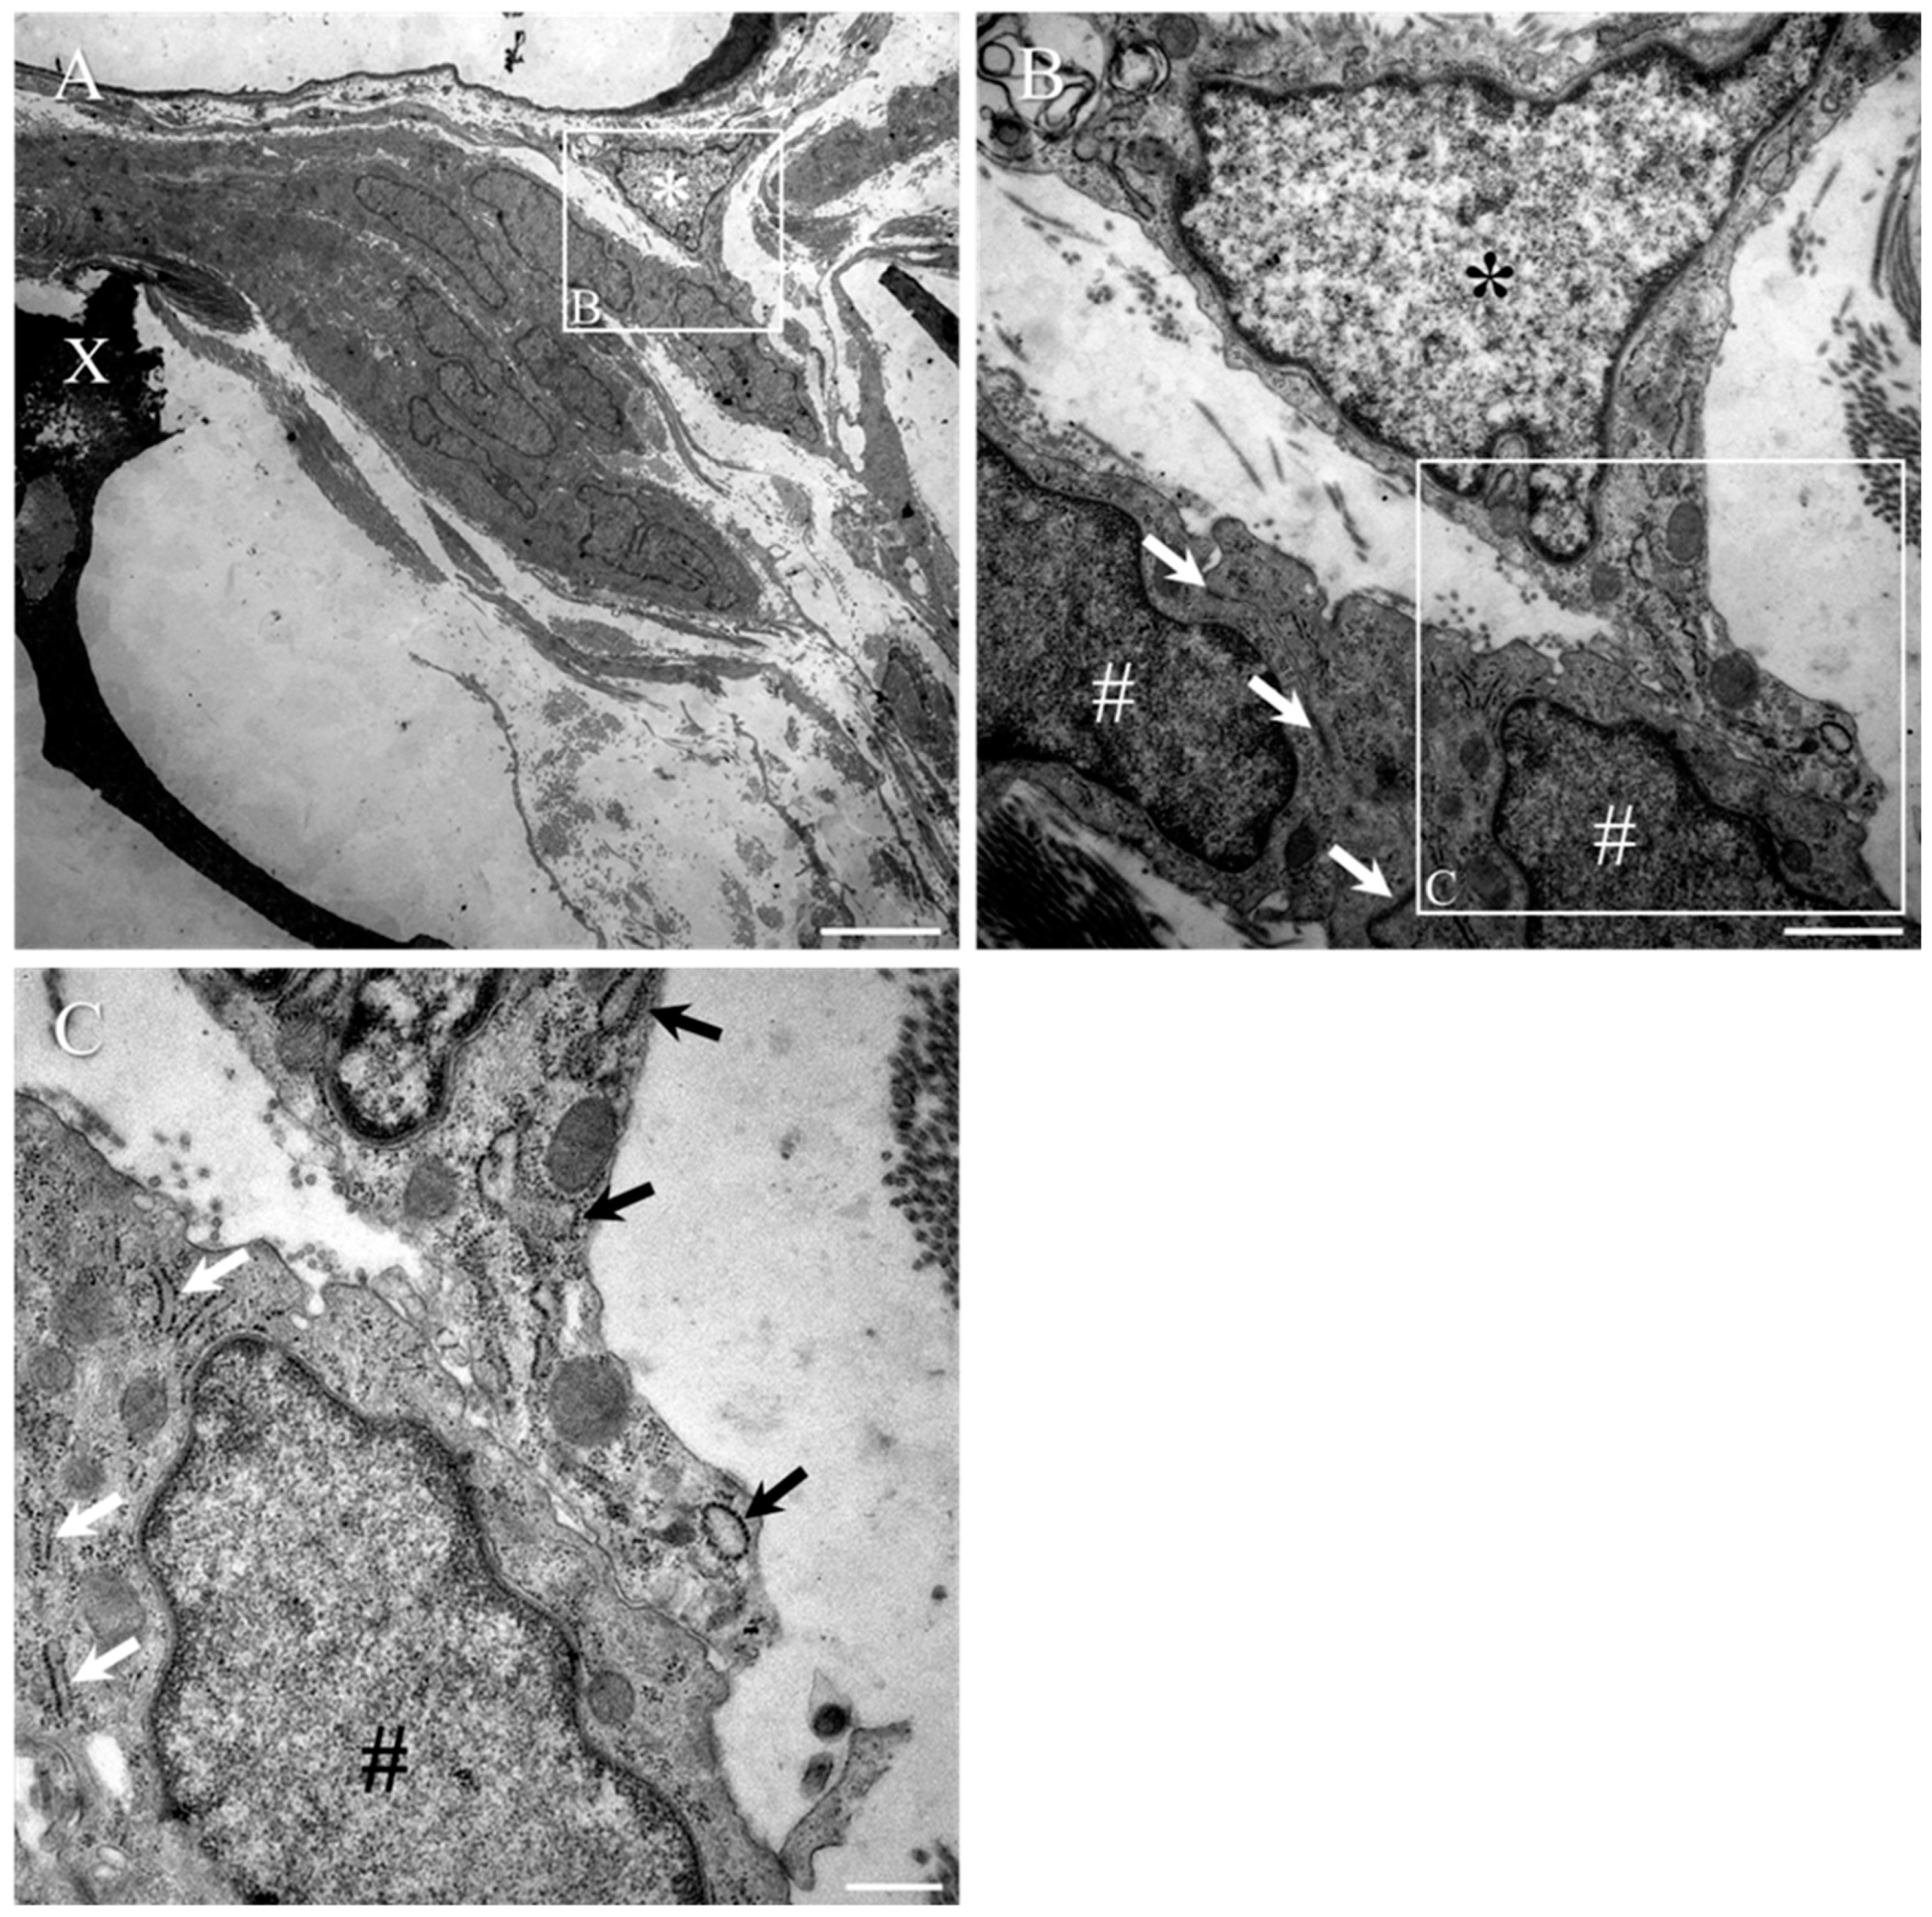

- Altinova, H.; Hammes, S.; Palm, M.; Achenbach, P.; Gerardo-Nava, J.; Deumens, R.; Fuhrmann, T.; van Neerven, S.G.A.; Hermans, E.; Weis, J.; et al. Dense fibroadhesive scarring and poor blood vessel-maturation hamper the integration of implanted collagen scaffolds in an experimental model of spinal cord injury. Biomed. Mater. 2020, 15, 015012. [Google Scholar] [CrossRef] [PubMed]

- Altinova, H.; Hammes, S.; Palm, M.; Gerardo-Nava, J.; Achenbach, P.; Deumens, R.; Hermans, E.; Fuhrmann, T.; Boecker, A.; van Neerven, S.G.A.; et al. Fibroadhesive scarring of grafted collagen scaffolds interferes with implant-host neural tissue integration and bridging in experimental spinal cord injury. Regen. Biomater. 2019, 6, 75–87. [Google Scholar] [CrossRef] [PubMed] [Green Version]